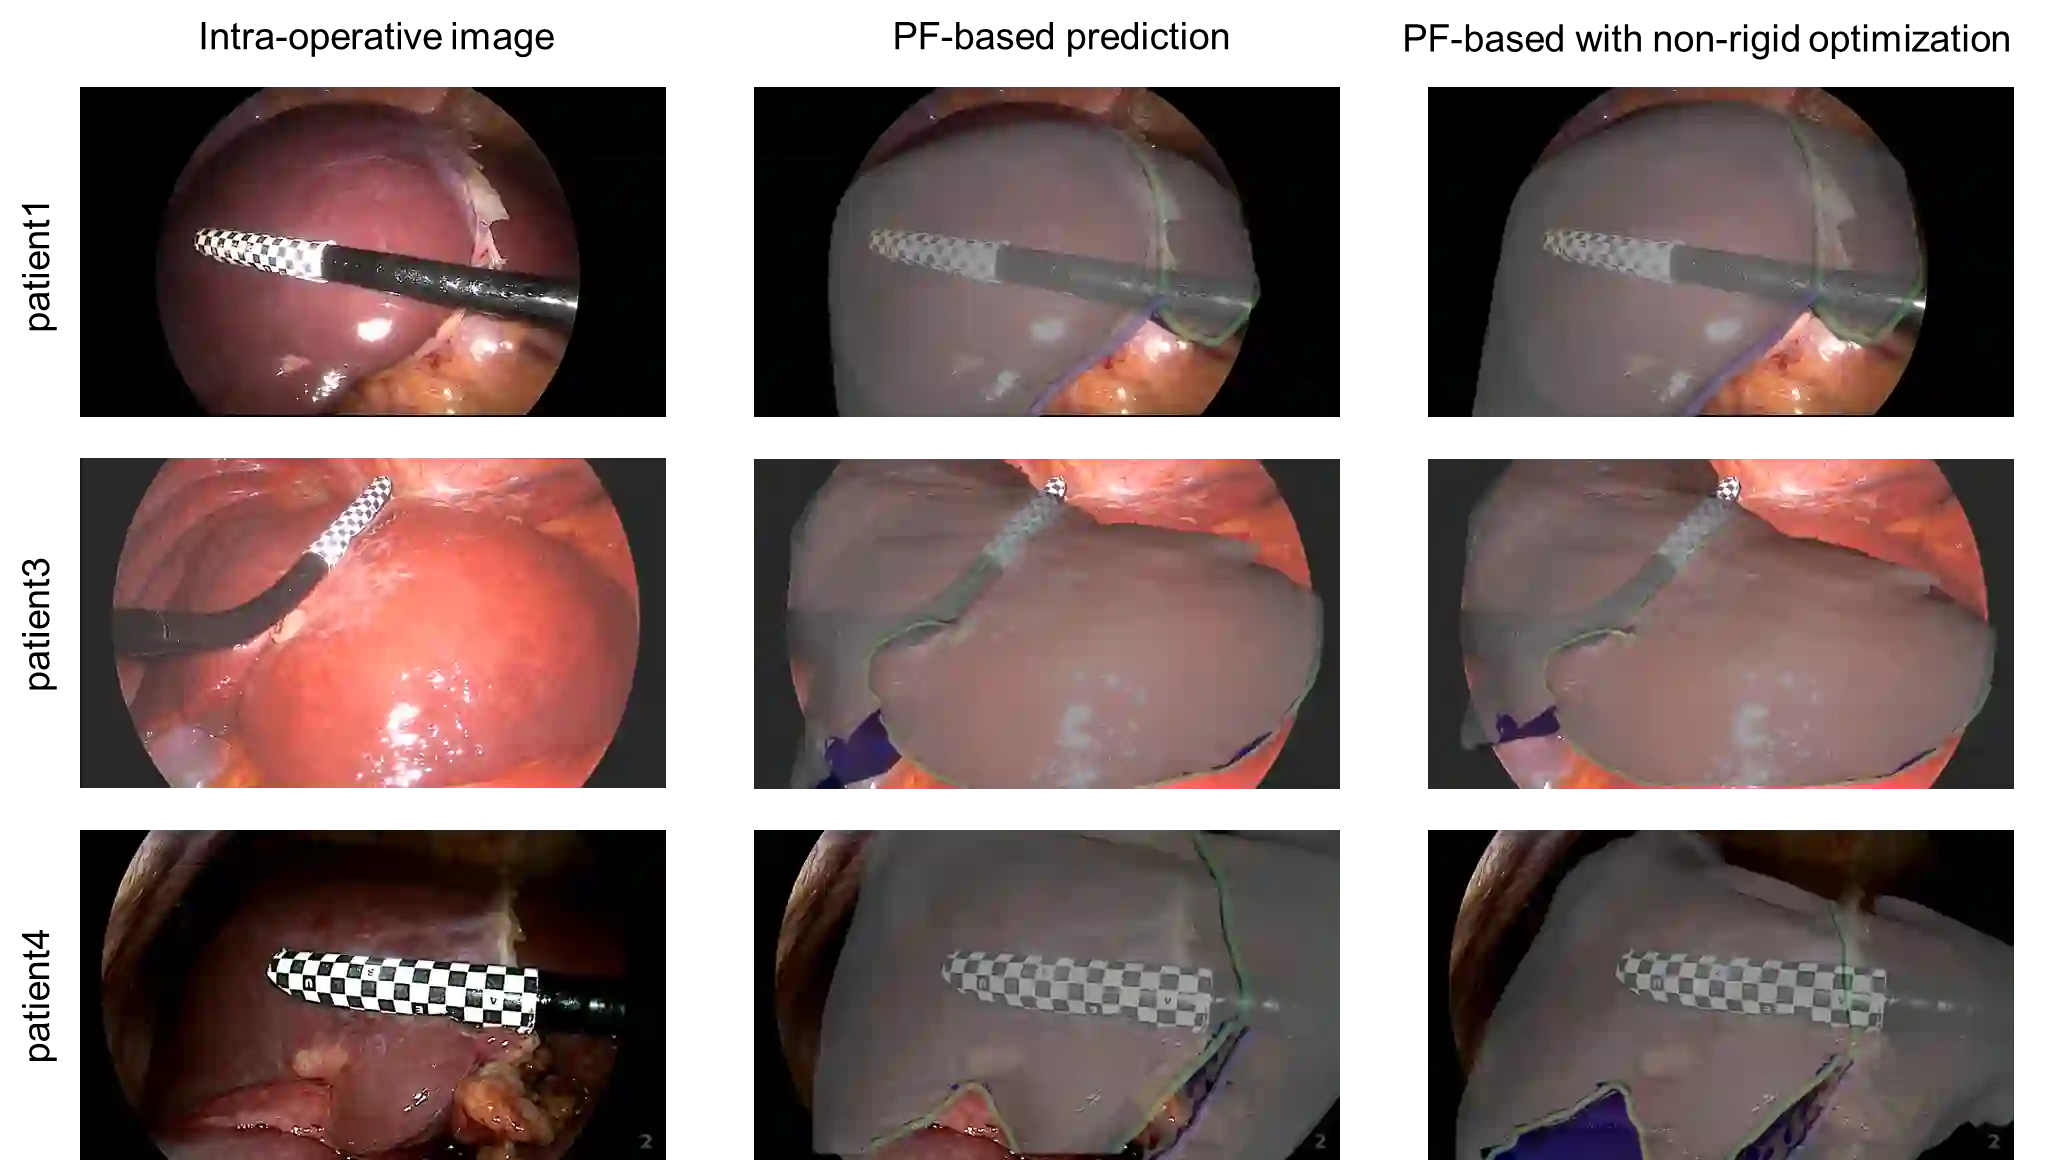

Augmented reality can improve tumor localization in laparoscopic liver surgery. Existing registration pipelines typically depend on organ contours; deformable (non-rigid) alignment is often handled with finite-element (FE) models coupled to dimensionality-reduction or machine-learning components. We integrate laparoscopic depth maps with a foundation pose estimator for camera-liver pose estimation and replace FE-based deformation with non-rigid iterative closest point (NICP) to lower engineering/modeling complexity and expertise requirements. On real patient data, the depth-augmented foundation pose approach achieved 9.91 mm mean registration error in 3 cases. Combined rigid-NICP registration outperformed rigid-only registration, demonstrating NICP as an efficient substitute for finite-element deformable models. This pipeline achieves clinically relevant accuracy while offering a lightweight, engineering-friendly alternative to FE-based deformation.